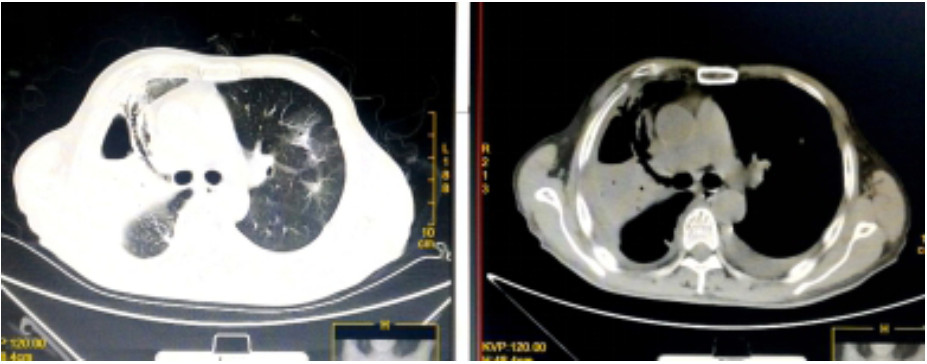

入院诊断“社区获得性肺炎”。予无创呼吸机支持(FiO2 75%),经验性予以美罗培南静脉泵入1.0 g 2次/d、磷酸奥司他韦口服75 mg 2次/d、莫西沙星静脉滴注0.4 g 1次/d。入科后治疗4 h仍无尿,且呼吸困难进行性加重,血氧饱和度进行性下降,氧合指数109 mmHg,予以经口气管插管接呼吸机辅助通气及连续性血液净化等治疗。机械通气后,吸出大量灰褐色痰,且病情进展快,短时间无法脱机拔管,12月17日气管切开。12月17日复查血常规:血白细胞2.49×109/L,中性粒细胞百分比0.925,血红蛋白70 g/L,血小板62×109/L。停用莫西沙星改用利奈唑胺0.6 g静脉滴注2次/d。12月19日胸部CT示,⑴双肺散在多发感染性病变,右侧为著;⑵右肺空腔伴气液平;⑶右侧胸腔积液(图 2)。12月19日血白细胞3.7×109/L,中性粒细胞百分比0.882,淋巴细胞百分比0.098,血红蛋白78 g/L,血小板115×109/L,入科后立即送检的血、痰培养回报均阴性。12月20日肺泡灌洗液病理回报镜下见炎症细胞、吞噬细胞及菌丝样物,未发现恶性细胞(图 3)。12月21日痰宏基因组学检测回报:肺炎链球菌(序列数113 916)、屎肠球菌(序列数1 307)、铜绿假单胞菌(序列数16)。12月20日及24日肺泡灌洗液、血培养均回报为屎肠球菌,药敏试验结果示,对氨苄青霉素、环丙沙星、红霉素、庆大霉素、青霉素耐药;对替考拉宁、替加环素、利奈唑胺、万古霉素、奎奴普丁/达福普丁敏感。继续利奈唑胺600 mg 2次/d,总疗程62 d。治疗期间血红蛋白在66~91 g/L,血小板均在(100~300)×109/L。12月26日CT引导下经皮肺组织穿刺术,并送检病理细胞学及组织培养,结果显示符合炎症性病变改变,病原学阴性。2020年1月9日脱离呼吸机,1月14日转入普通病房,1月23日拔出气管切开套管,2020年2月13日复查胸部CT病灶有所吸收(图 4),2月24日好转出院。出院半年后电话随访,当地医院复查胸部CT示病灶较前明显吸收,已经正常工作。

| 图 2 患者2019年12月19日胸部CT结果(双肺散在多发感染性病变,右侧为著;右肺空洞伴气液平面;右侧胸腔积液) |